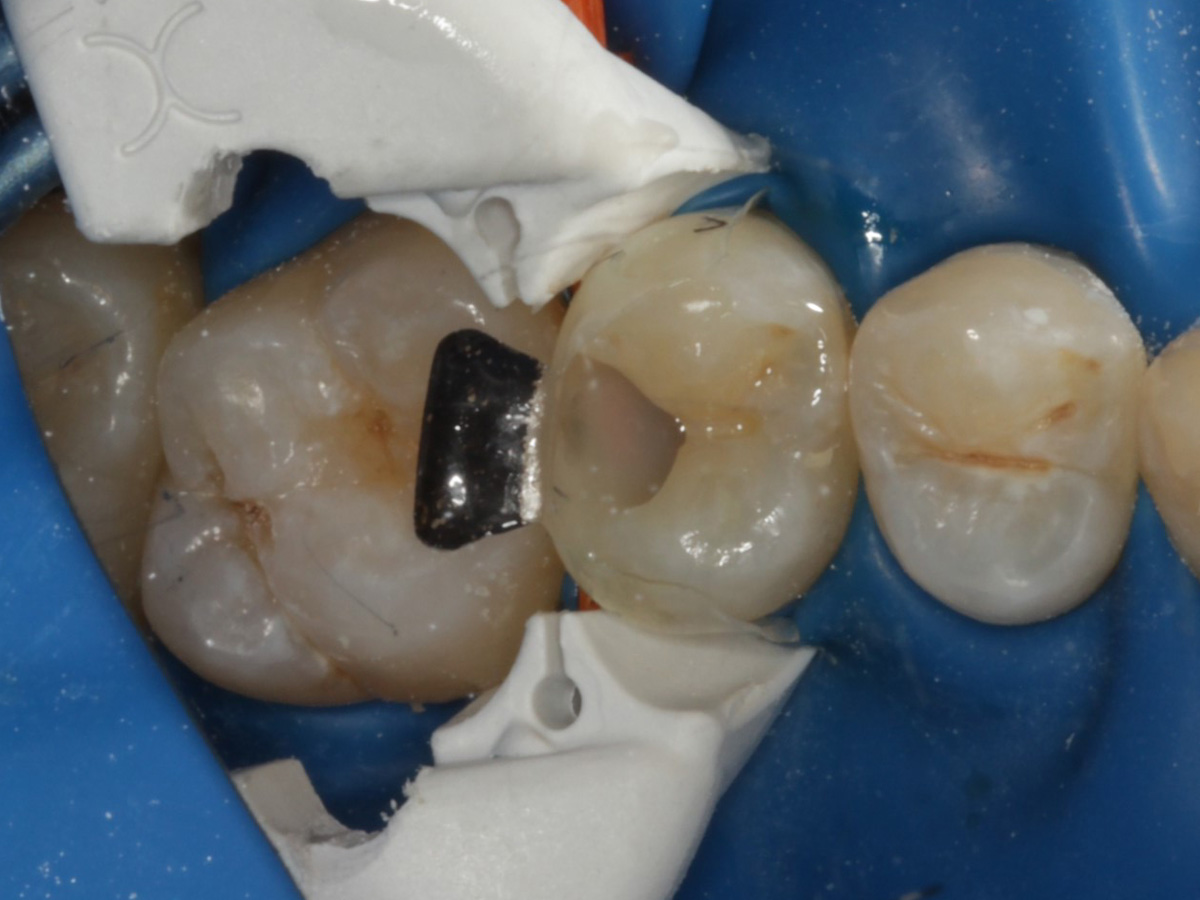

Abbildung 1

Approximalraumkaries an Zahn 25 distal

Abbildung 2

Bissflügelröntgenaufnahme